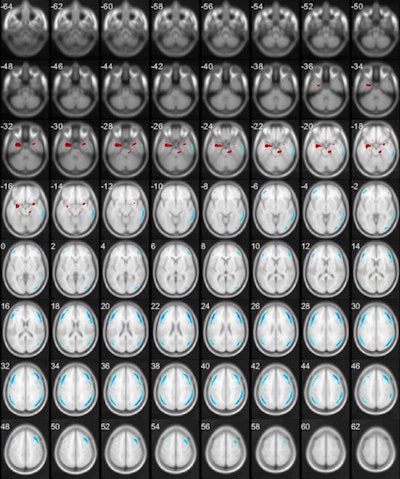

Based on a height threshold criteria of T = 4.38 and an extent threshold > 100 voxels, statistic parameter mapping demonstrated that the major depression patient group had significant regional metabolic differences (clusters of continuous voxels) as compared with the group without major depression. Five significant hypo- and three hypermetabolic clusters from CT contrast maps were localized on glass-brain view and were consistent with previously published brain metabolic changes in major depression patients, the authors reported.